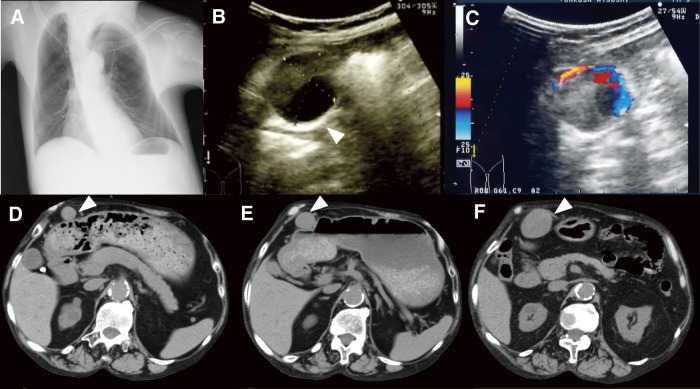

52岁男性脊柱侧凸伴寻常型银屑病,接受英夫利昔单抗治疗,表现为右侧大胃网膜动脉瘤(GEAA)。手术切除后,发现了前交通动脉和腹主动脉的其他动脉瘤。组织病理学检查显示假性动脉瘤伴组织血栓和明显的急性炎症,包括内侧壁中性粒细胞浸润。尽管培养阴性,但不能排除感染相关的血管损伤。本病例强调了慢性炎症性疾病中罕见的免疫介导的血管病理,强调了急性炎症和银屑病相关免疫失调在内脏动脉瘤形成中的潜在作用。

A 52-year-old man with scoliosis and psoriasis vulgaris, treated with infliximab, presented with a large right gastroepiploic artery aneurysm (GEAA). Following surgical resection, additional aneurysms of the anterior communicating artery and abdominal aorta were identified. Histopathological examination revealed a pseudoaneurysm with organizing thrombus and marked acute inflammation, including neutrophilic infiltration of the medial wall. Despite negative cultures, an infection-related vascular insult could not be excluded. This case highlights a rare immune-mediated vascular pathology in the context of chronic inflammatory disease, emphasizing the potential role of acute inflammation and psoriasis-associated immune dysregulation in visceral artery aneurysm formation.